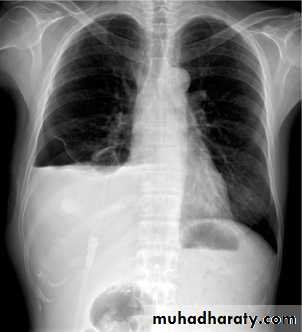

Consolidation is a radiological sign that refers to non-specific air-space opacification on a chest radiograph or chest CT. Many things can fill the alveolar spaces, including fluid (heart failure), pus (pneumonia), blood (pulmonary haemorrhage) and cells (lung cancer)

Consolidated areas are radio opaque on chest radiograph and chest CT compared to normally air filled lung tissue.

Lobar consolidation

Where increased density/opacity is seen in individual lung lobes. Sharp delineation can be seen when consolidation reaches a fissure, since it does not cross. Air bronchograms can also be seen due to bronchi becoming visible against the dense diseased tissue. Volume loss is usually not seen..